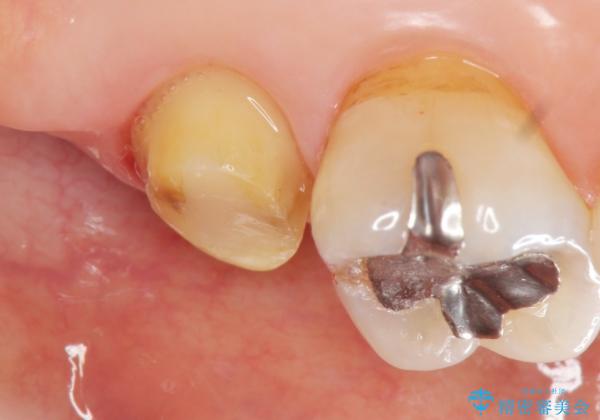

クラウンの将来的な虫歯の再発を防ぐために周囲の歯ぐきを切除することで歯の高さを出し安定した歯周環境にしたのち噛み心地の良いゴールドクラウンを製作します。

クラウンを装着した歯の虫歯の再発を防ぎ長い予後を期待するために削った箇所をしっかりとかぶせる適合の良さが必要はもちろんですが、セメントの漏洩を防ぐためにクラウンの十分な支台高径を歯周外科を行い獲得しました。